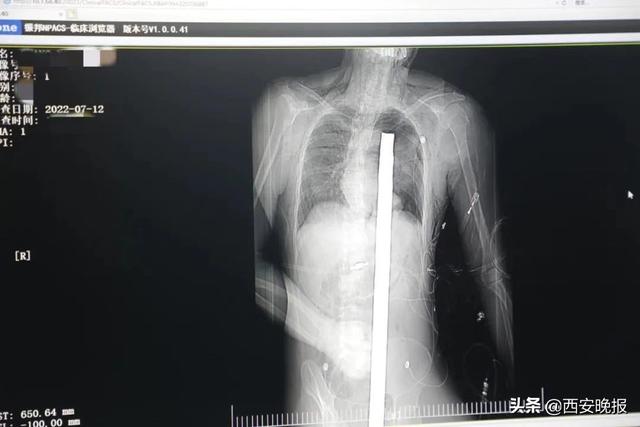

时间就是生命。医院第一时间开辟绿色通道,急诊X光片及CT显示:异物经会阴部贯穿盆腔、腹腔到达左侧胸腔主动脉弓水平。胸外、心外、肝胆外科、胃肠外科,泌尿外科及麻醉科等多学科专家联手,对患者进行纵劈胸骨+前外侧开胸探查+气管及主支气管修补+肺修补+血胸清除+开腹探查止血+腹膜后及盆腔探查。

术中探查发现,长120厘米直径3厘米的螺纹钢经患者右侧会阴部穿入,伤及直肠,途径膀胱后方,左侧髂总动静脉之间伤及左肾后,经胰腺后方在肝脾之间穿破膈肌,在下肺静脉前方穿入左肺穿破气管及左右主支气管膜部,止于主动脉弓下水平,穿入体内的部分达到75厘米。